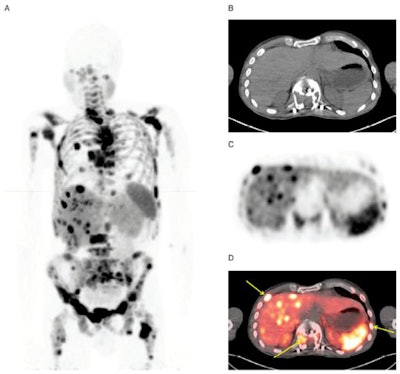

The trial included 63 subjects (mean age, 54.4 ± 15.7 years) with known or suspected NETs. Of that group, 42 patients were positive for NETs and 21 were healthy volunteers. All subjects underwent a PET/CT scan an average of 63 minutes after a single intravenous dose of Cu-64 DOTATATE at 148 MBq (range, 132-163 MBq). The scan covered the skull to the midthigh in 3D mode, with an image acquisition time of five minutes per bed position over an approximately 30-minute total scan time.

Three board-certified nuclear medicine physicians evaluated the results and "categorized subjects as 'disease' or 'no disease' based only on Cu-64 DOTATATE tumor uptake," the authors explained.

Collectively, the trio achieved sensitivity of 91%, while specificity ranged from 80% to 96% and positive predictive value ranged from 83% to 96%. Negative predictive value was 90% among the three reviewers, with accuracy ranging from 95% to 93%. The readers also differentiated between metastatic and localized disease with sensitivity and specificity of 100%, which the researchers attributed to Cu-64 DOTATATE's "excellent quality images ... to facilitate high interreader and intrareader agreement on the presence or absence of metastatic or localized disease."